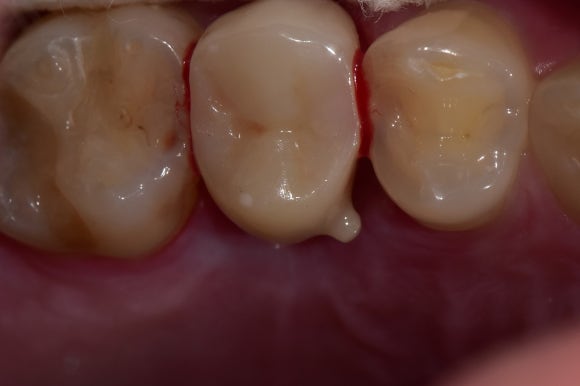

20250411

그래도 육안상으로는

치아가 멀쩡하게 잘 있는 것 같아 보이는데요?

사실은 그렇지 않습니다.

충치라는 녀석은

언제나 치아에 작은 구멍을 뚫고

내면을 파먹는 식으로 진행이 됩니다.

파먹힌 치아는

얇은 껍데기만 남게되고,

어느 날 갑자기 밥을 먹다가 구멍이 나게되는 것이지요.

그러니,

치아에 구멍이 났다면 정말 심각한 상황이라고 보시면 됩니다.

어서 치과에 가셔야 합니다.